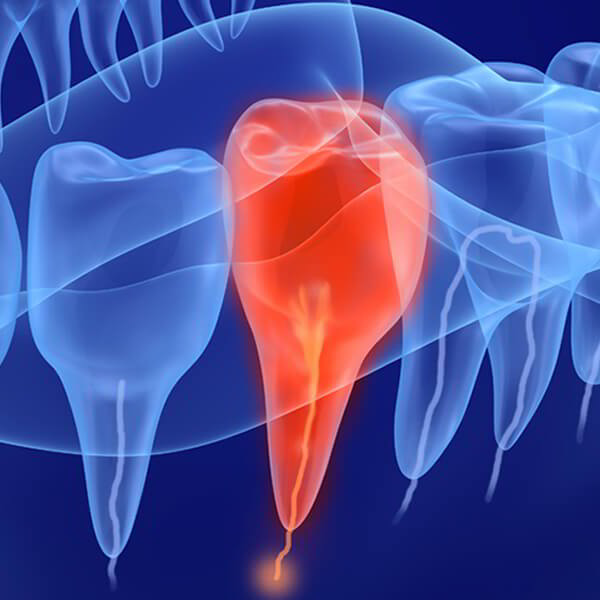

Types of dental surgery are often used such as: Wisdom teeth removal surgery Gingival surgery Root canal surgery Periodontal surgery Depending on the dental…